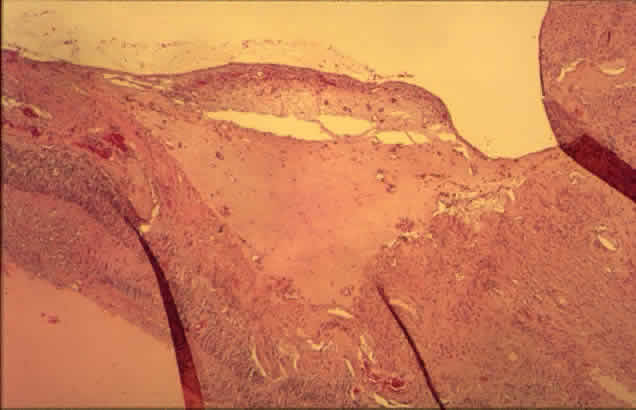

Histologically, new vessels develop between the retinal surface and the posterior surface of the formed vitreous (Fig. 12). With NVE, there is a demonstrable break through the internal limiting membrane (Fig. 13).20 Early-developing new vessels have lumina even at the proliferating tips.53 Active new vessels have endothelial cells and pericytes, with fenestrations. Morphologically, fenestrations are areas ranging from 40 to 80 nm in diameter where the cell membranes are focally fused, and are normal findings in capillaries outside of the retina and brain. They allow increased permeability and are responsible for the diffuse leakage of fluorescein seen from new vessels on angiography. Inactive or “ghost” new vessels are acellular, having lost both endothelium and pericytes.39 With time, fibrous tissue develops and accompanies the new vessels. The vessels themselves may leak and bleed into the vitreous, leading to visual loss.

Fig. 12. Neovascularization at the disc with fibrous proliferation. The fibrovascular membrane overlies the internal limiting membrane, which is wrinkled (arrows). The retinal detachment is artifactual. (PAS, × 19.5)

Fig. 13. Neovascularization away from the disc. The fibrous tissue has contracted, imparting a triangular shape to the membrane. Active new vessels are present throughout. The dark folds are artifactual. (H&E, × 31.25)